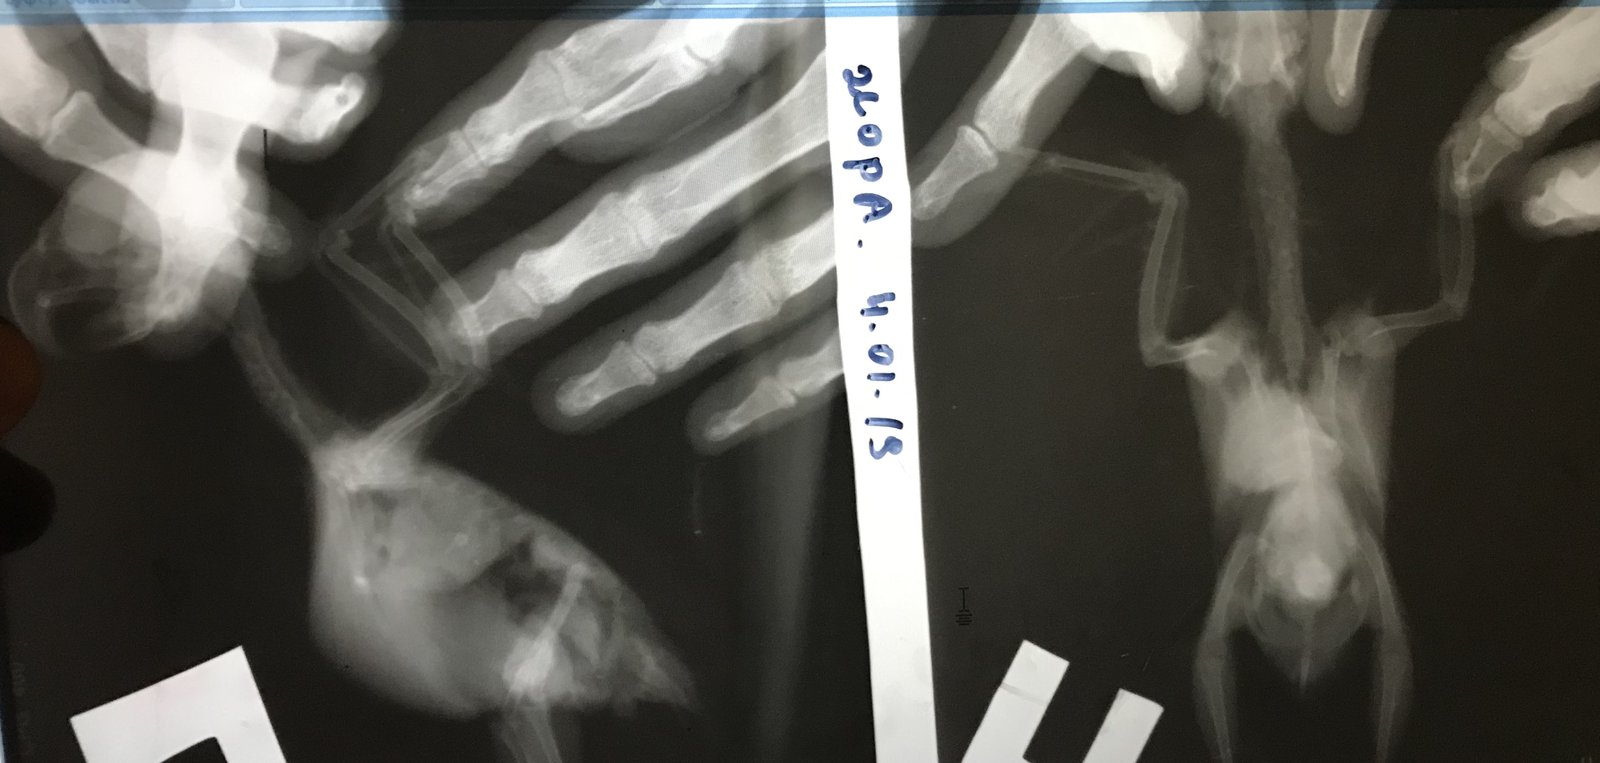

Помогите пожалуйста птице 5лет какарик стал плохо дышать отвезли к орнетологу сделали ренген подозрение на лейкому сказали ничем не могут помочь птица умерает выписали обезбаливаюшие   Помогите

BD2AE629-ADE5-45BA-9A1E-316B379FC932.jpeg

A13CFB29-6689-4A87-8C5E-02B351B2B34C.jpeg